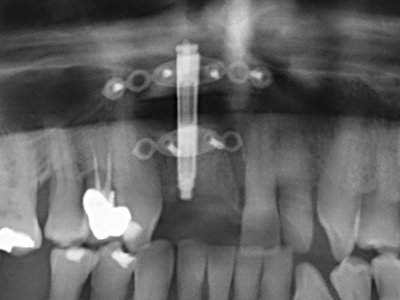

Fig. 11: El ortopantomograma posoperatorio presenta el aumento vertical y la elevación del suelo del seno.

Fig. 12: Después de seis meses de cicatrización se muestra una cresta maxilar vital con unas dimensiones suficientes en todas las direcciones.